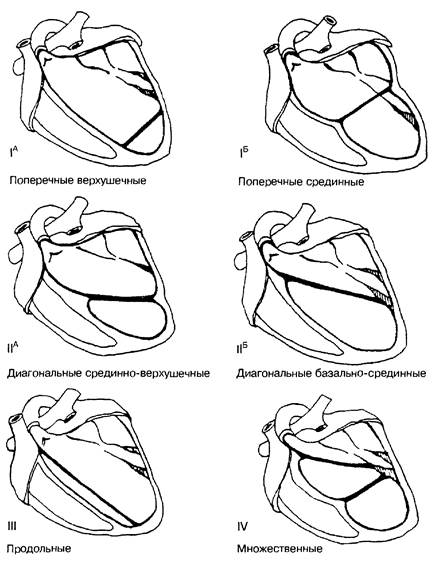

Рис. 1. Схематическое изображение различных вариантов расположения ложных хорд левого желудочка сердца (по Т.Ф.Перетолчиной, 1996; Э.В.Земцовскому, 2000).